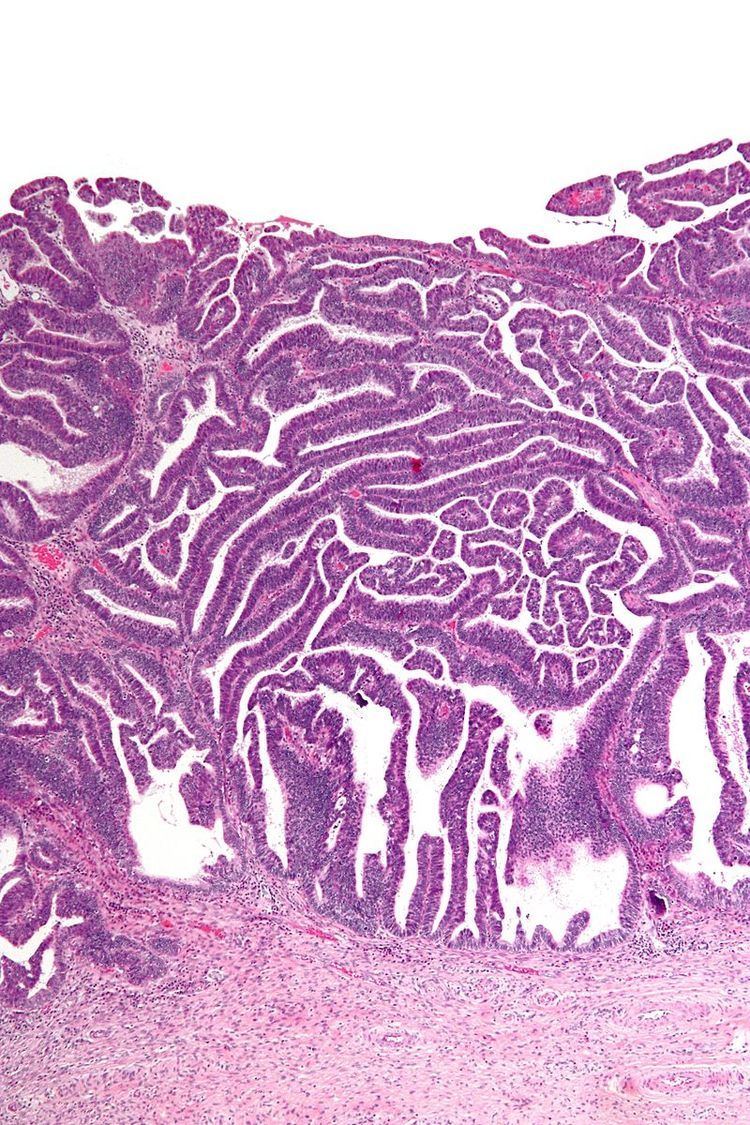

The name of the lesion describes it microscopic appearance. It has nipple-like structures with fibrovascular cores (papillae) that are long in relation to their width (villus-like), which are covered with a glandular pseudostratified columnar epithelium.